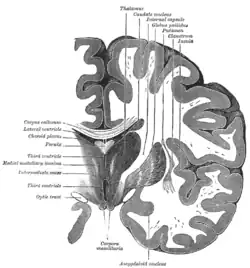

Horizontal section of right cerebral hemisphere.

Human brain frontal (coronal) section